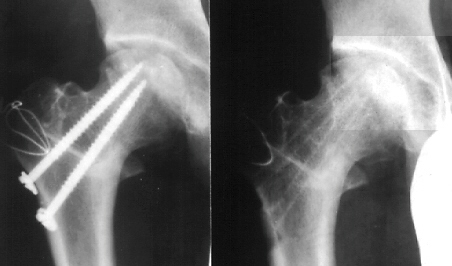

PATIENT 2.

W.H.. 12-year-old-girl. Post-traumatic avascular necrosis of rt.

femoral head. She sustained the right femoral neck fracture by

falling from a balcony.

After bed-rest for 2 weeks, she started walking with crutches.

She completely returned to normal activities 6 months after the

trauma. She was beginning to complain of the right hip pain 2

years after the trauma. A large area of avascular necrosis was

in weight bearing surface of the femoral head.

The large posterior surface of the femoral head remained intact.

A Sugioka osteotomy was performed with 90 degrees of anterior

rotation and 15 degrees of varus angulation. After post-operative

non-weight-bearing for 4 weeks, and partial-weight-bearing for

6 weeks, she has had neither limping nor pain so far.